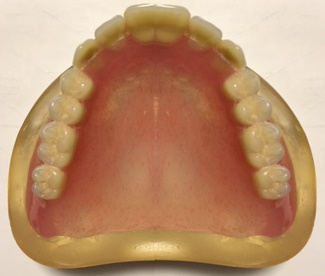

●レジン床の総義歯(保険適応)

主にレジンというプラスチック系の材料からできている入れ歯です。修理が比較的容易で、保険が適用されるので治療費が比較的安価であるという利点があります。プラスチックであるため、食べ物の熱さや冷たさの伝わり方が鈍い、やや壊れやすいという欠点もあります。